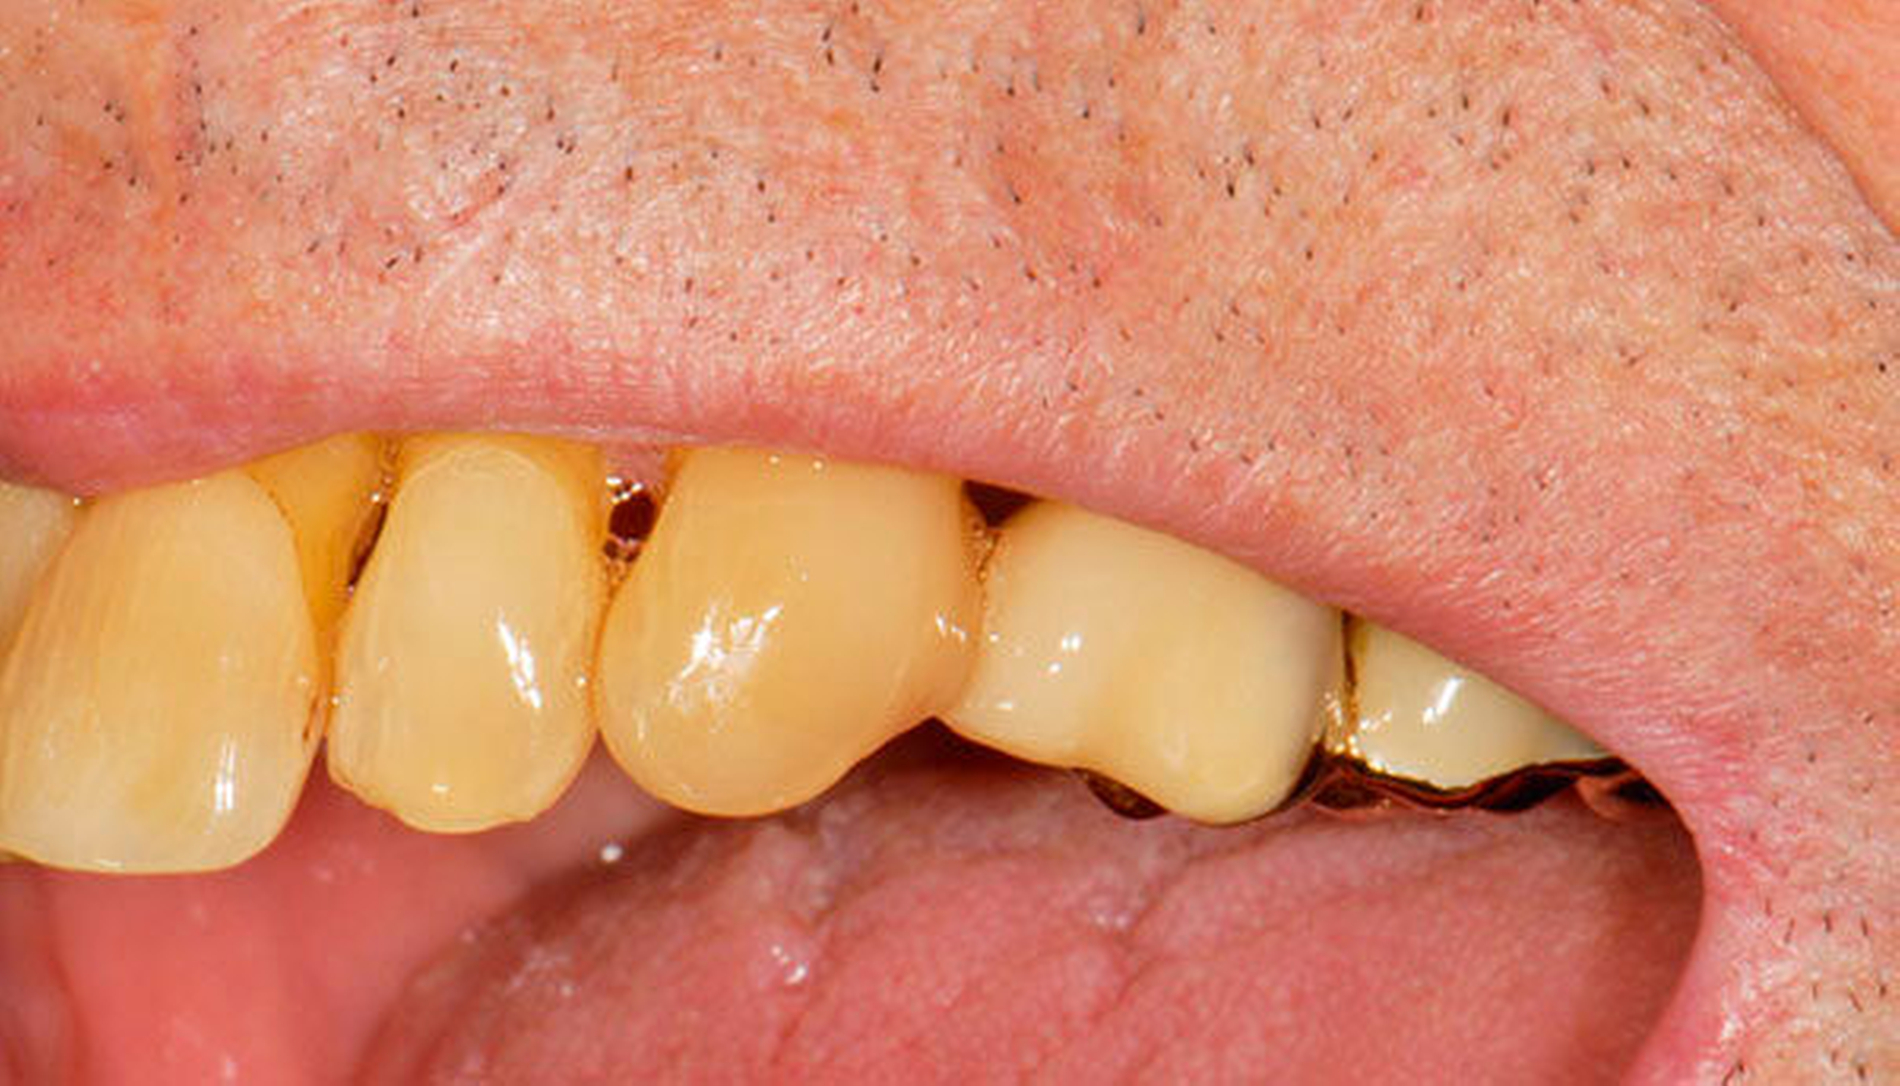

Abbildung 1 A-I: 84-jähriger Patient mit arterieller Verschlusskrankheit (Claudicatio intermittens)

Senioren haben – wie oben ausgeführt – immer häufiger zahlreiche eigene Zähne. Im Fall von Lückenbildungen müssen diverse Behandlungsalternativen in Erwägung gezogen werden. Dazu zählen neben klassischen prothetischen und implantologischen Versorgungen auch andere Optionen (Tabelle 1). Nicht jede Lücke muss geschlossen werden. Wenn funktionell und ästhetisch keine relevanten Einschränkungen bestehen, kann auch ein Monitoring (Belassen und Beobachten) eine gute Lösung sein [Staehle, 2010; Listl et al., 2016]. Daneben kommen zuweilen Zahnumformungen und -verbreiterungen (Abbildung 1) oder direkte Freiendanhänger aus Komposit als Behandlungsmittel zum Lückenschluss in Betracht [Staehle, 2007, 2009, 2010, 2012, 2017; Staehle et al., 2014, 2015a, b; Frese und Staehle, 2018]. Schließlich ist für Patienten, bei denen aufwendiger festsitzender Zahnersatz nicht möglich ist und die keine herausnehmbare prothetische Versorgung wünschen, die Verfolgung des Prinzips der verkürzten Zahnreihe [Walter, 2016] zuweilen eine gute Alternative. Zur praktischen Realisierung dieses Konzepts kann heute die konservierend-restaurative Zahnheilkunde (zum Beispiel über Zahnverbreiterungen und -anhänger, eventuell in Kombination mit Schienungen) ebenfalls viel beitragen.